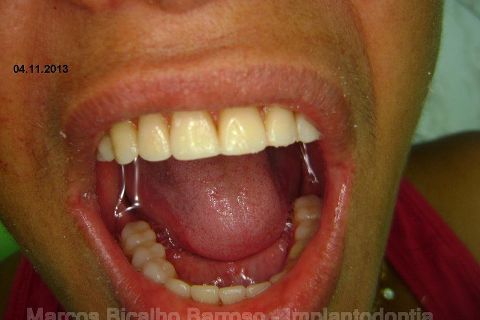

Atualização do caso clínico que já postei, "REABILITAÇÃO EM MAXILA ATRÓFICA COM IMPLANTES", um caso que inclui expansão do rebordo estreito com cinzel e martelo, expansores rosqueáveis, enxerto e instalação dos implantes distais inclinados tangenciando seio maxilar. Inclui esvaziamento do forame nasopalatino e preenchimento com biomaterial para instalação de dois implantes próximos dele. Cirurgia realizada em única sessão, com instalação dos 6 implantes. Para os colegas que não conheceram e/ou esqueceram da apresentação, este é o resumo do caso na fase cirúrgica.http://www.youtube.com/watch?v=BtvexFexRPA&hd=1

FASE PROTÉTICA DA REABILITAÇÃO EM MAXILA ATRÓFICA...incluindo a reabertura, instalação dos minipilares e PTR provisória reembasada sobre os cilindros de proteção.